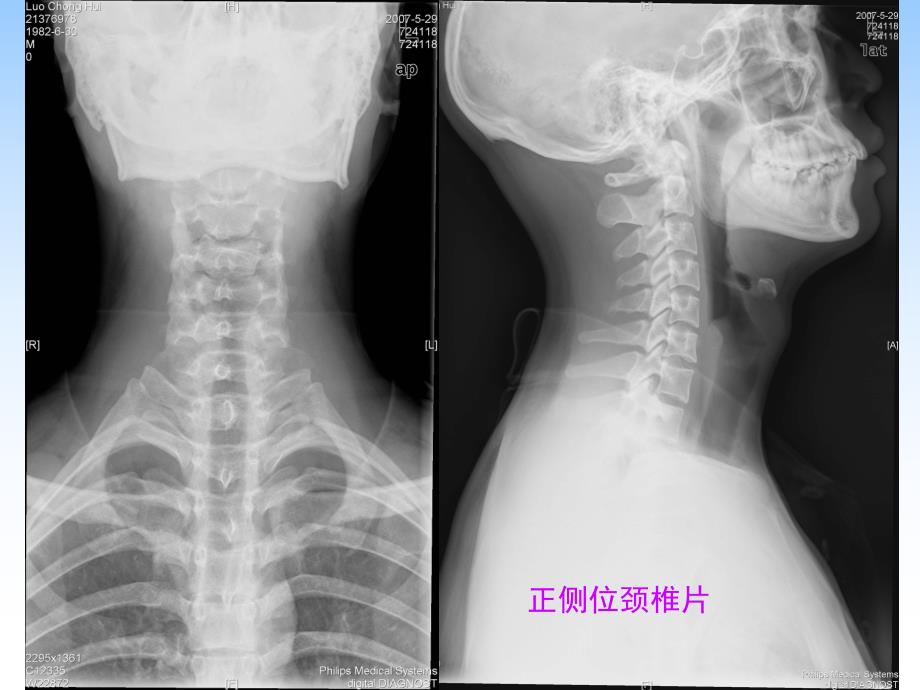

1、椎间盘突出症的影像诊断椎间盘突出症的影像诊断 复习有关部位的正常影像解剖复习有关部位的正常影像解剖正侧位颈椎片颈椎双斜位片正侧位胸椎片椎间隙椎间孔关节突腰椎正侧位片颈椎CT腰椎CT腰椎CT胸椎MRI 椎间盘在椎间盘在T1WI呈低信号,分不清髓核与纤维呈低信号,分不清髓核与纤维环,环,T2WI纤维环呈低信号,髓核呈高信号,正常纤维环呈低信号,髓核呈高信号,正常情况下约情况下约9030岁以上的受检者在椎间盘中央可见岁以上的受检者在椎间盘中央可见水平走行的低信号带,为纤维组织造成,属正常现水平走行的低信号带,为纤维组织造成,属正常现象。随含水量减少,正常椎间盘象。随含水量减少,正常椎间盘T2信号逐渐

4、间盘突出症的临床及影像认识也不断深入,给临床治疗及疗效观察提床及影像认识也不断深入,给临床治疗及疗效观察提供客观依据。供客观依据。1、脊椎生理曲度改变;侧弯畸形;脊椎失稳、脊椎生理曲度改变;侧弯畸形;脊椎失稳2、椎体前阴影增宽(下段颈椎多见)、椎体前阴影增宽(下段颈椎多见)3、椎间隙变窄、椎间隙变窄4、骨赘形成、骨赘形成5、小关节增生、小关节增生6、椎间孔狭小、椎间孔狭小7、椎管狭窄、椎管狭窄8、韧带钙化、韧带钙化9、椎间盘真空现象、椎间盘真空现象10、许莫氏结节形成(颈椎少见)、许莫氏结节形成(颈椎少见)X线表现线表现颈椎骨质增生、椎间孔狭窄等颈椎骨质增生、椎间孔狭窄等椎管造影:椎管造影:方